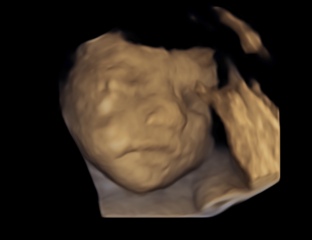

I had a private scan yesterday at 26+1, baby was not playing nicely, kept moving everywhere, wouldn’t face the scanner and at one point totally turned their back 😂

It was just a standard scan so the lady changed to 4D so we got to see the face 🥰

It was wonderful being able to see the movement and feel it at the same time ❤️